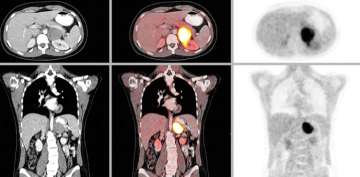

Pheochromocytoma Scan >

CT or MRI of the abdomen will almost always identify a pheochromocytoma. Additional specialized imaging such as MIBG (meta-iodobenzylguanidine) or Ga-68 Dotatate PET/CT scan can help to confirm a pheochromocytoma and identify multiple tumors or metastatic spread.